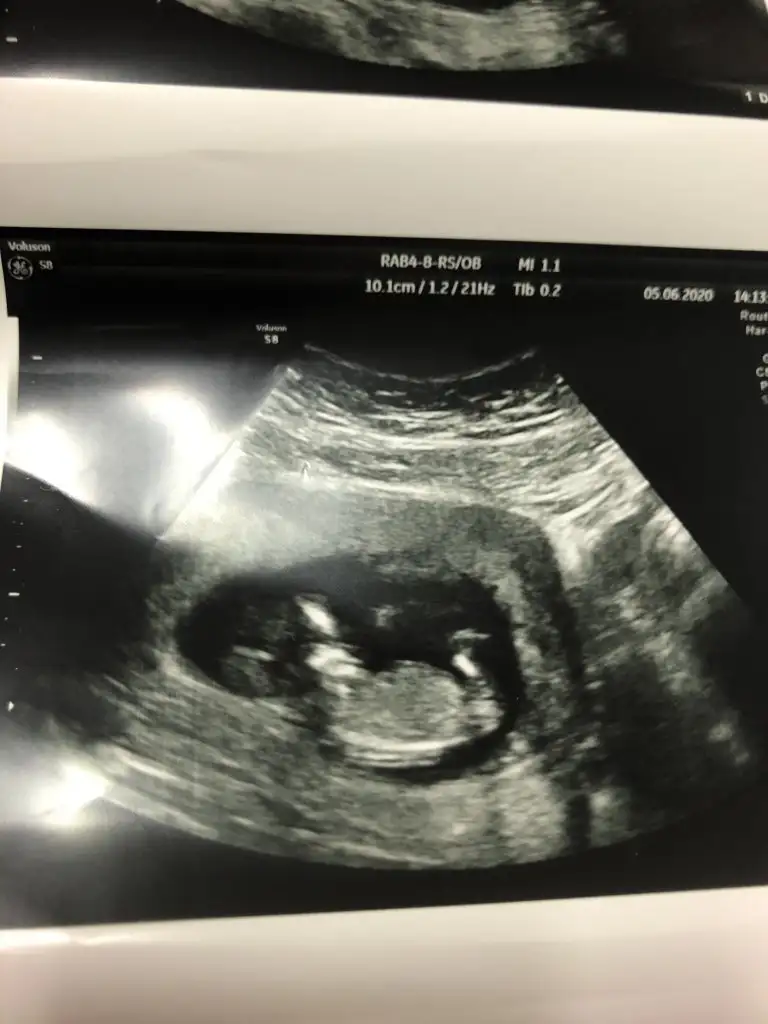

Karından bakıldı ise kız en iyi nub için 11 12 13 hafta paylaşınIkra meyra canım bakar mısın ilk fotoyu atmıstım daha önce ikinci foto 7. Haftadan

Canım ilk foto için karındansa erkek demiştin bende 7. Hafta fotosunu atayım dedim 10. Haftamda tekrar gideceğim o zaman yine atayımKarından bakıldı ise kız en iyi nub için 11 12 13 hafta paylaşın

Evet biliyorum ilkte erkrek demiştim kese konumu pek guven vermiyor o nedenle 11 12 13 hafta usg olursa paylalın 10 haftada değilde 11 haftada gitsenizCanım ilk foto için karındansa erkek demiştin bende 7. Hafta fotosunu atayım dedim 10. Haftamda tekrar gideceğim o zaman yine atayım

Hem net değil hemde 11 12 13 hafta olmalıBana da tahmin yapabilir misiniz 15+1 göstermedi cinsiyeti bugün bıcırık :)Ikra meyra

Mrb 13 haftalik olduk cok sukurKız gibi net de değil kız sanki 12-13 olunca tekrar usg paylaşın

bu da diger acidan fotografi ayagi kapatmis gibi amabu bu haftaki goruntusu 12. hafta gecen hafta erkek demistiniz ama emin olamamistiniz@ikrameyra